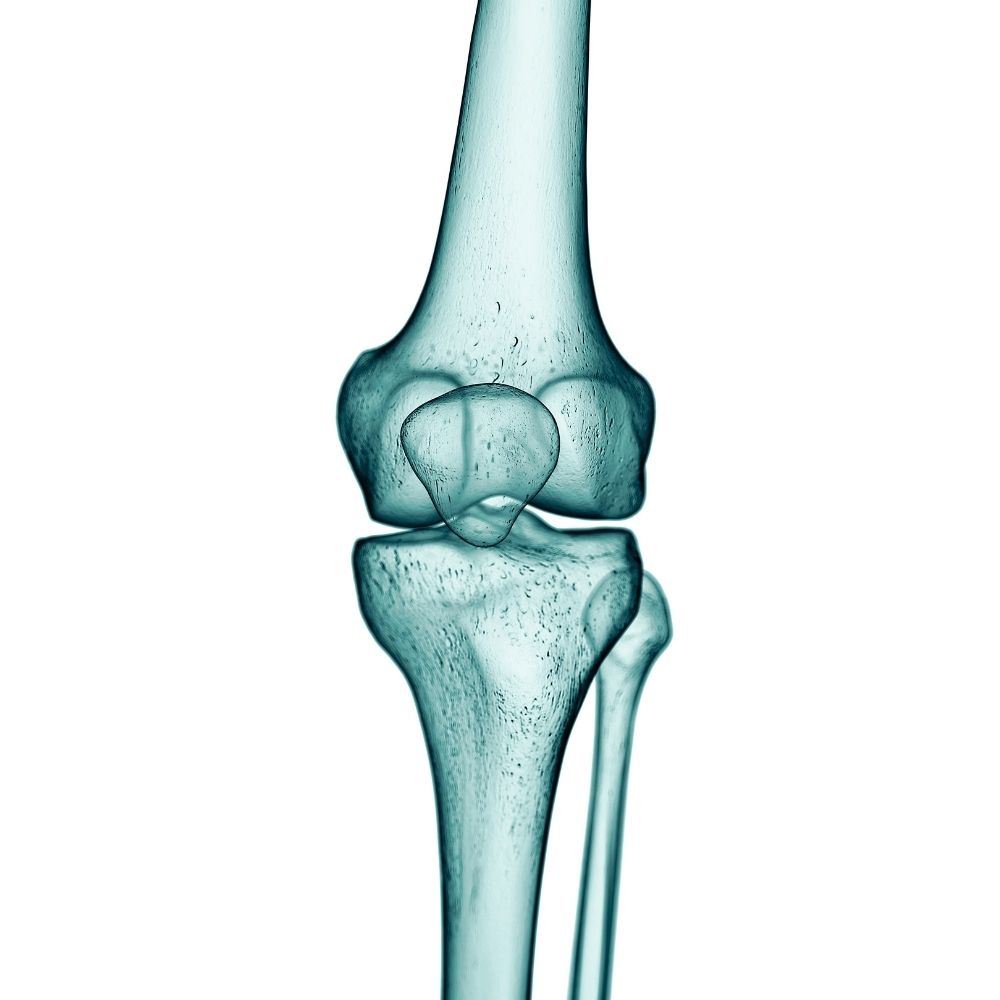

Artrosi del ginocchio

gonartrosi

L’artrosi del ginocchio (gonartrosi) è una patologia cronica e progressiva di frequente riscontro, caratterizzata dall’usura della cartilagine che riveste l’articolazione.